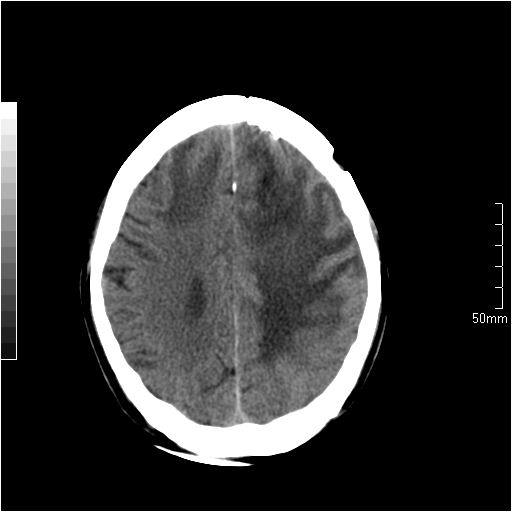

以下是引用天南地北在2007-6-25 12:39:00的发言:[br]有占位效应[br]支持术后复发

以下是引用zjzjr在2007-6-25 12:38:00的发言:[br]左侧复发,右侧转移。